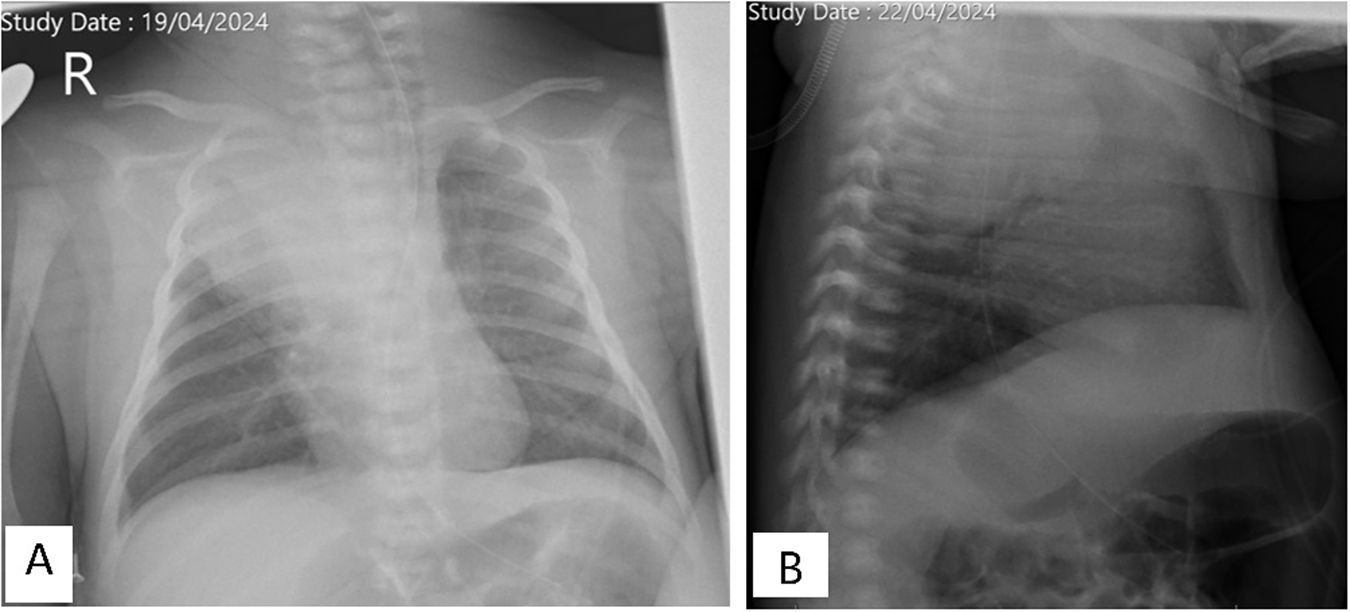

La radiografía de tórax mostraba una opacidad completa en el lóbulo superior derecho (fig. 1), mientras que las ecografías pulmonares seriadas eran normales (fig. 2A). La ecografía torácica realizada desde el plano supraclavicular mostraba una consolidación bien definida sugestiva de masa torácica (fig. 2B y vídeo 1) que se evidencia en la TAC (fig. 3). La biopsia confirma el diagnóstico de neuroblastoma congénito.

Radiografía de tórax. A)Proyección anteroposterior. Opacidad completa en el lóbulo superior derecho, con desplazamiento mediastínico hacia el lado contralateral, con buena aireación de los demás campos pulmonares, sin derrame pleural asociado. B)Proyección lateral. Opacidad en el segmento posterior del lóbulo superior del pulmón derecho, de morfología nodular.